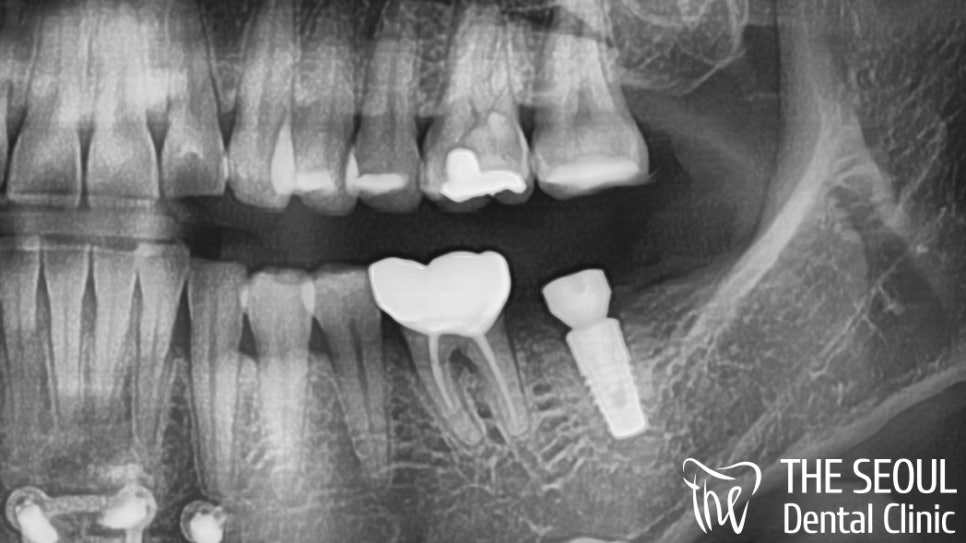

초진 사진을 살펴보면

좌측 아래 어금니 부위에

임플란트 픽스쳐가 심어져 있었습니다.

힐링까지 결합이 되어있는 것으로 보아

치료를 꽤 진행했었네요.

어떤 사정인지 모르겠지만..

이렇게 두고 크라운을 올리지 않다니ㅜㅜ